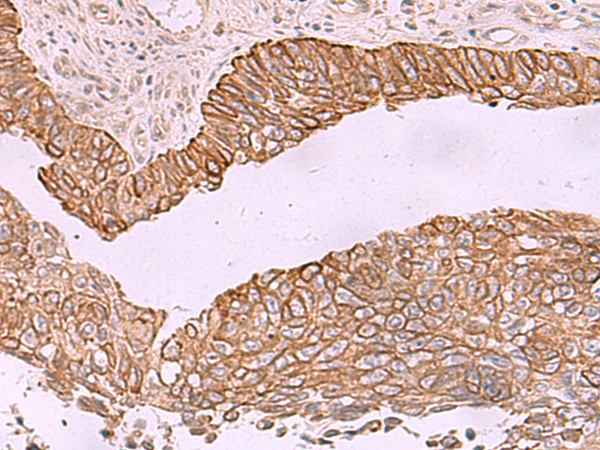

IHC positive control: |

Human lung cancer |

IHC Recommend dilution: |

50-300 |